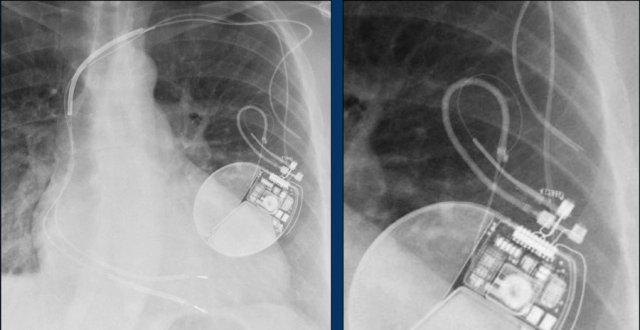

Đây là hình ảnh máy tạo nhịp hai thất với ba điện cực.

Điện cực tạo nhịp nhĩ phải nằm ở tiểu nhĩ phải.

Điện cực này đi xuống dưới vào nhĩ phải trước, sau đó vòng lên trên và ra trước, nơi nó được neo chặt vào các bè cơ của tiểu nhĩ.

Điện cực thất trái đi qua nhĩ phải và xoang vành, cuối cùng được đặt ở phía sau vào một tĩnh mạch tim bên trái.